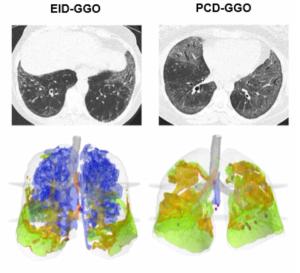

Study Looks at Combining PCCT and Lung Texture Analysis for Evaluating ILD in Patients with Systemic Sclerosis